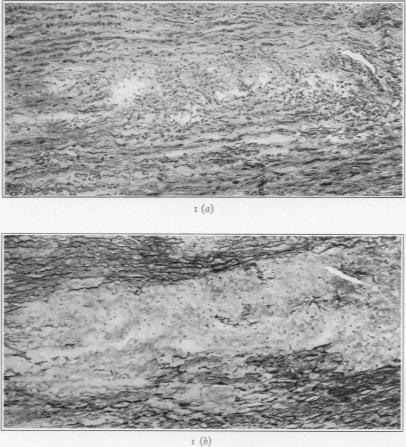

Medionecrosis Aortae Idiopathica Cystica.

Am J Pathol. 1932 Nov;8(6):717-734.3.